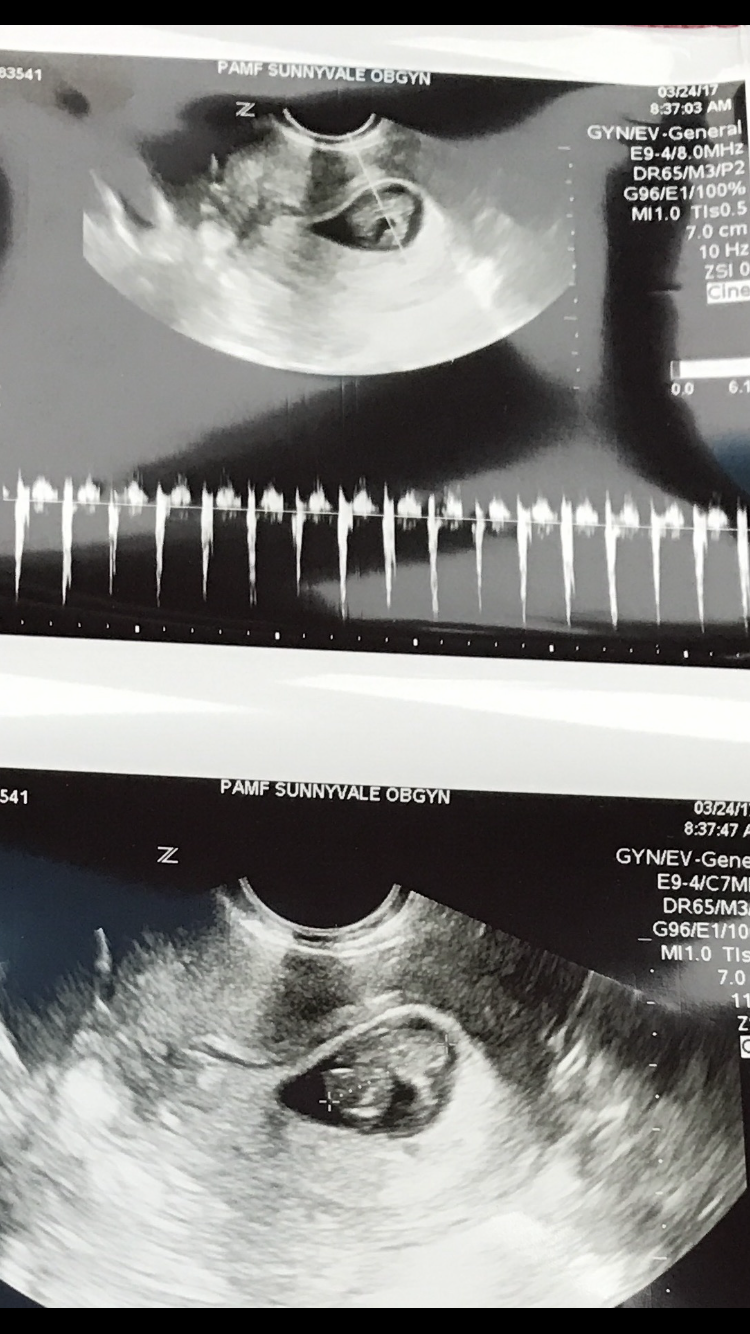

On March 4th, we received some of the best news ever, that after trying, hoping and praying, I was pregnant, blessed with a miracle from God with our natural pregnancy. We are so happy, grateful and humbled by this gift and all the responsibilities that come with it.

I’ll be 9 weeks pregnant tomorrow, and already two family members who know had a surprised reaction along with their happiness, one even was surprised we were trying. I’m going to blog about what it’s like to be pregnant at this age, the experiences good and bad, and hopefully share fun memories and experiences. If you have questions, feel free to ask.